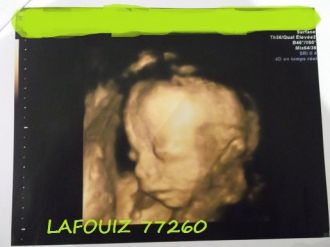

écho du 2e trimestre

Alors enfin nous avons fais l'écho du 2e trimestre !!

Bébé va très bien, il pèse déjà 500g mesure a peu près 20 cm! Il bouge très bien !! il avait les jambes croisées et les bras derrière la tête tranquille enfaite !

Puis voila le moment ou gygy nous demande si nous voulons savoir le sexe, et bien sur nous voulons!!!

Nous allons être les heureux parents d'un petit garçon !!!

Voila une petit écho de notre fils !!

Message déposé le 05.10.2011 à 23:05 - Commentaires (0)